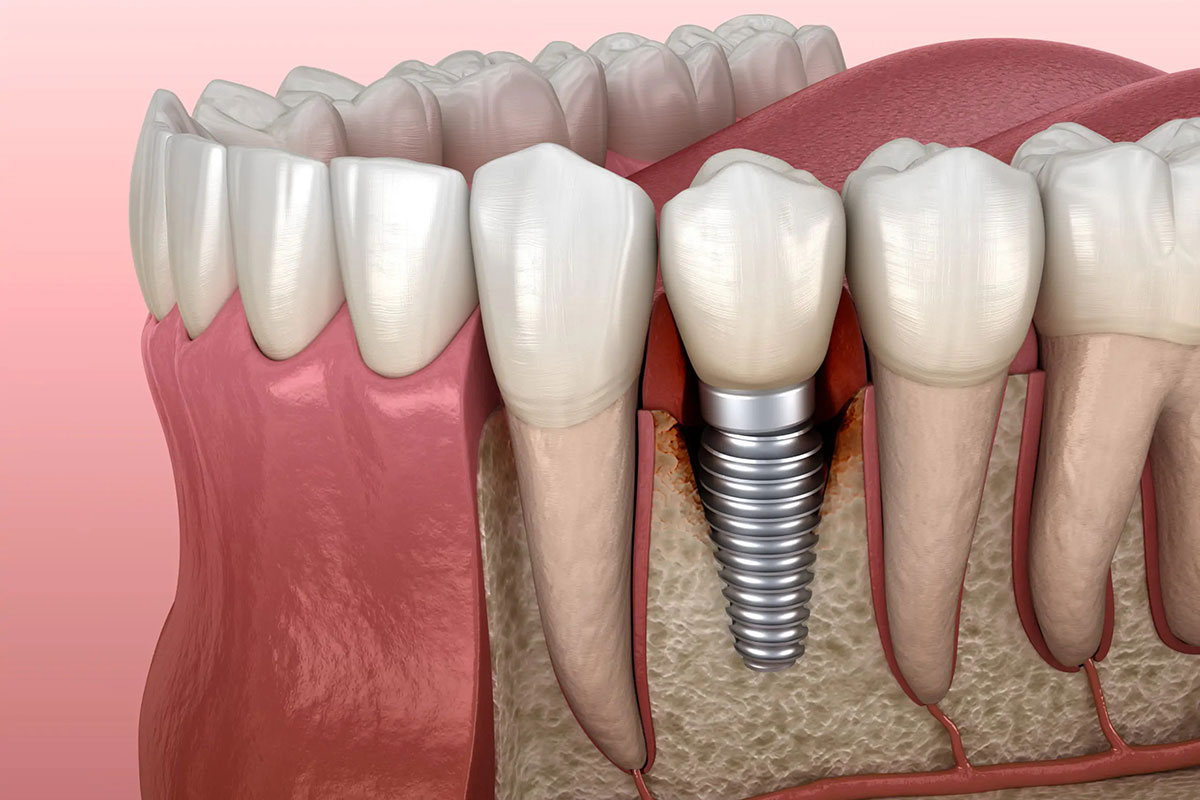

Quando si parla di igiene orale quotidiana, la maggior parte delle persone pensa subito allo spazzolino e al dentifricio. In realtà, per mantenere davvero sani denti e gengive, esiste un alleato fondamentale che spesso viene sottovalutato: il filo interdentale. Perché lo spazzolino da solo non basta Lo spazzolino è essenziale per rimuovere la placca batterica dalle…